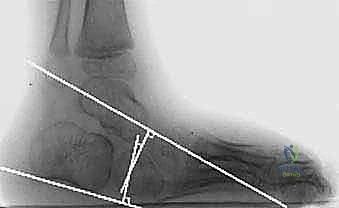

التقييم السريري الدقيق: اختبار سيلفرفسكولد (Silfverskiöld Test)

لا يقرر الأستاذ الدكتور محمد هطيف إجراء الجراحة إلا بعد فحص سريري دقيق. يُعد اختبار سيلفرفسكولد حجر الزاوية في هذا التقييم.

* الخطوة الأولى: يقوم الطبيب بثني ركبة المريض بزاوية 90 درجة، ثم يحاول ثني الكاحل للأعلى (Dorsiflexion). إذا تحسن مدى حركة الكاحل، فهذا يعني أن القصر محصور في العضلة التوأمية فقط (لأن ثني الركبة أدى إلى إرخائها).

* الخطوة الثانية: يقوم الطبيب بفرد ركبة المريض تماماً، ويحاول ثني الكاحل للأعلى. إذا كان الكاحل متيبساً في كلتا الحالتين (الركبة مثنية والركبة مفرودة)، فهذا يؤكد أن القصر يشمل وتر أخيل بأكمله (بما في ذلك العضلة النعلية). هنا تصبح عملية إطالة وتر أخيل بالانزلاق المفتوح هي الحل الأمثل.